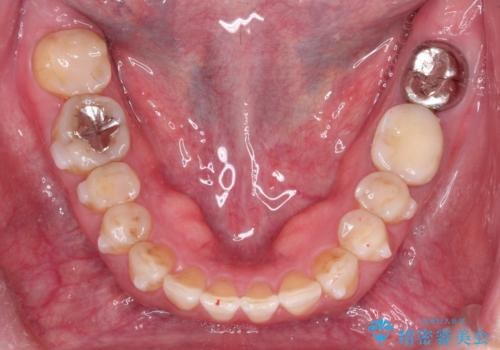

- 前歯のガタガタを主訴に来院されました。

上の歯の前突も気になってたため、奥歯の遠心移動も行いながらインビザラインにて治療を行いました。

今回は奥歯の遠心移動とIPRを行って配列しています。